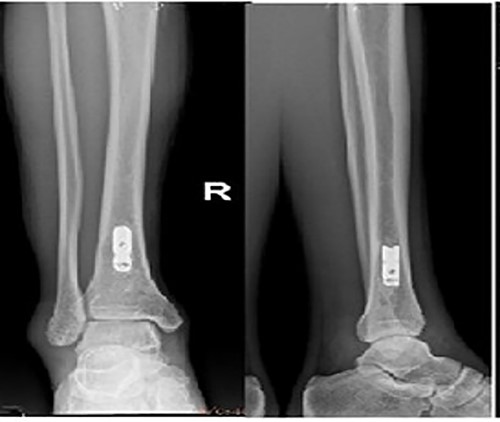

Preoperative X-ray films showing union of the right tibial fracture associated with a broken intramedullary nail remaining distal to the tibia.

A 48-year-old male patient was admitted for requesting removal of all internal implants in his body. He had a closed tibial shaft fracture caused by a collision 15 years prior and was treated with close reduction and intramedullary nailing fixation. Delayed healing occurred after the operation. A nail was broken at a distal locking screw hole. The fracture healed after plaster fixation for 3 months. The internal implant was removed 3 years after the fracture, but the distal end of the broken intramedullary nail could not be removed by the hook removal method and remained in the medullary cavity (Fig. 1). Both operations were performed in another hospital. One year prior to admission, the patient underwent open reduction and internal fixation in our hospital due to a fracture of the right distal radius, and the fracture healed after the operation. His function in the lower and upper limbs recovered well. It can be seen from the preoperative X-ray film that the remaining intramedullary nail was hollow; through measurement, it was known that the outer diameter of the broken nail was 10 mm, which was larger than the isthmus of the medullary cavity.